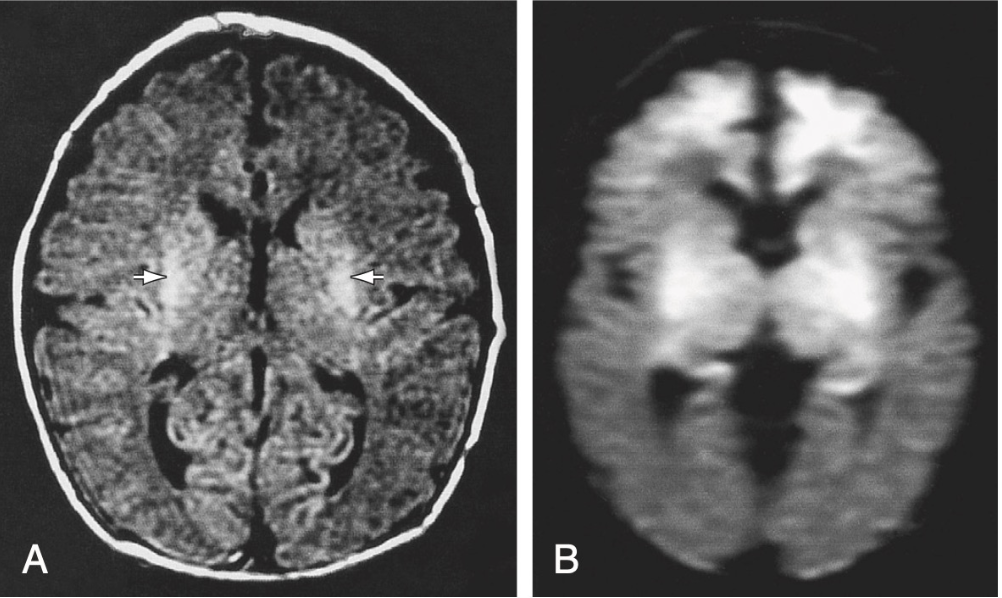

MRI

Most sensitive imaging method for detecting injury.

It will be performed within the first 3 to 5 days.